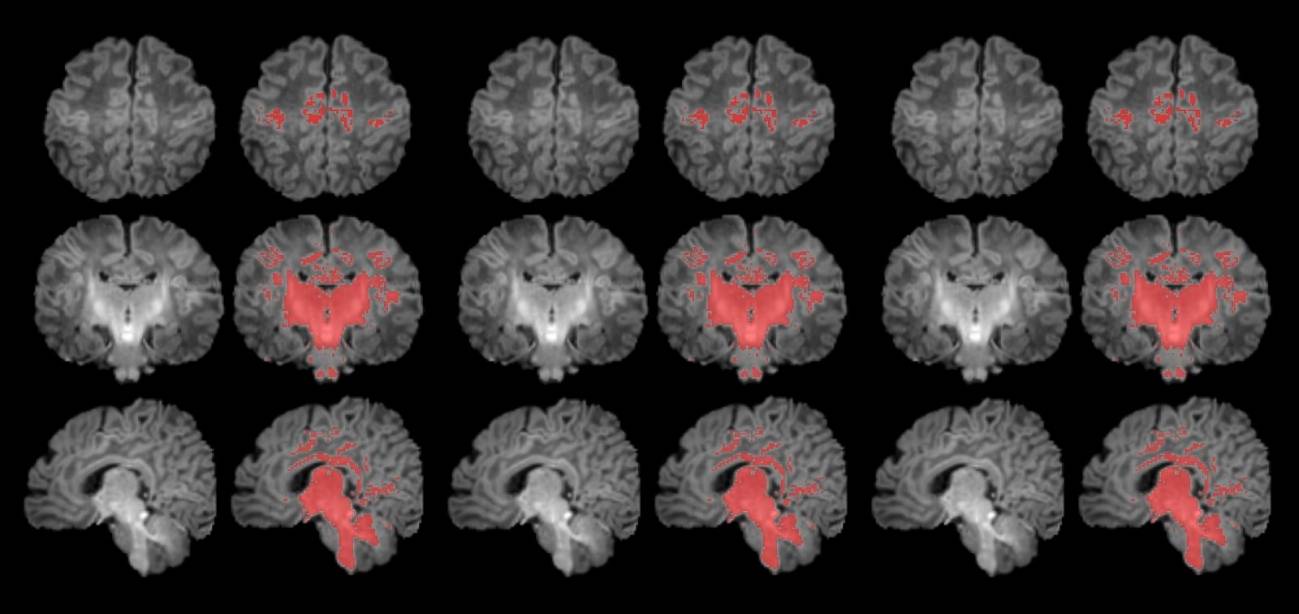

La mielinización es un proceso clave en la maduración del cerebro, en que la mielina recubre las conexiones neuronales y las hace eficientes para la transmisión de información. Los recién nacidos de madres expuestas a niveles más altos de partículas finas en suspensión durante el embarazo muestran una mielinización más lenta en esta etapa tan precoz de la vida.

En este sentido, según explica Gerard Martínez-Vilavella, investigador de la Unidad de Resonancia Magnética del Servicio de Radiología del Hospital del Mar, integrado en la red dibi, y del Instituto de Investigación del Hospital del Mar, “en el estudio vemos que el proceso de mielinización, un indicador de maduración cerebral que avanza progresivamente con el tiempo, presenta un ritmo más lento en los recién nacidos más expuestos a PM2.5 durante el embarazo”.

Para llevar a cabo el estudio se reclutó a mujeres embarazadas en seguimiento en el Hospital Clínic Barcelona, el Hospital de Sant Pau y el Hospital Sant Joan de Déu. Se monitorizaron los niveles de contaminantes atmosféricos a los cuales estaban expuestos durante la gestación y, después del parto, se seleccionó a 132 recién nacidos. A estos se les realizó una resonancia magnética antes de cumplir el primer mes de vida para observar el grado de maduración cerebral según sus niveles de mielinización.